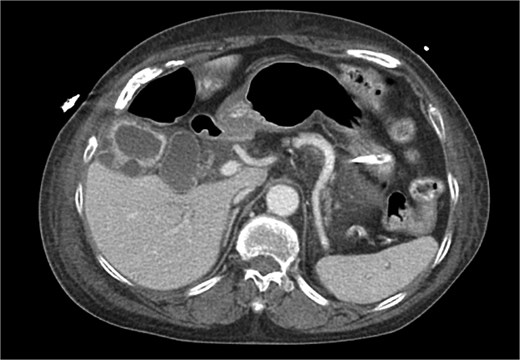

A 63-year-old female with a history of developmental delay, hypertension, hyperlipidemia, paroxysmal atrial fibrillation, hyperparathyroidism status post-parathyroidectomy, and ESRD on intermittent hemodialysis who presented for a scheduled left kidney transplant. Her post-operative course was complicated by subcapsular hematoma resulting in significant blood loss and requiring resuscitation in the trauma-surgical intensive care unit (TSICU); acute hypoxic respiratory distress on post-operative day (POD) 2, necessitating reintubation and escalating vasopressor support; and bacteremia and xanthogranulomatous cholecystitis identified on POD 3, confirmed by imaging (Figs 1 and 2) and blood cultures positive for Klebsiella pneumoniae and Enterobacter cloacae with Cefotaxime-Munich (CTX-M) resistance.

CT chest abdomen pelvis with IV contrast axial view. Gallbladder wall hyperenhancement and multiple intramural hyperattenuating nodes are again apparent in axial imaging.